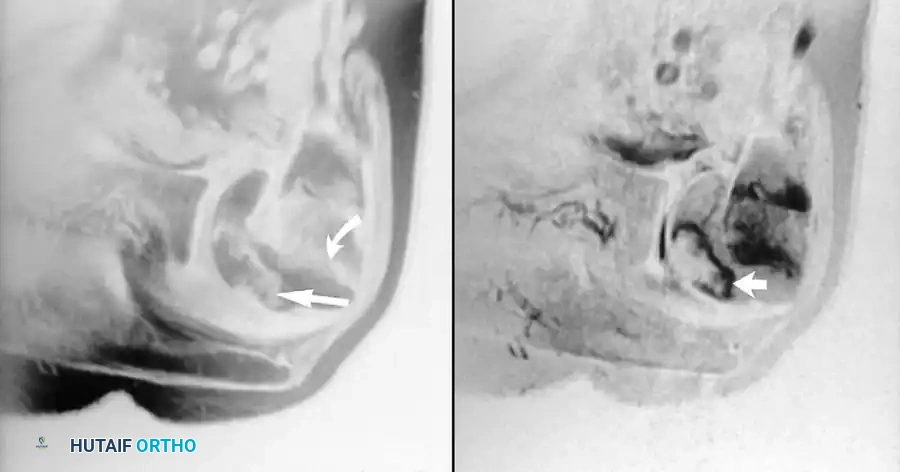

Carpal Tunnel Syndrome and Osteonecrosis

MRI has a limited, albeit specific, role in the evaluation of carpal tunnel syndrome. Although this remains a strictly clinical and electrodiagnostic (EMG/NCS) diagnosis, axial imaging with T2 weighting can clearly display space-occupying masses (e.g., lipomas, ganglions, anomalous muscle bellies) within the confines of the carpal tunnel, as well as edema and swelling of the median nerve.

Furthermore, MRI is highly sensitive and useful in detecting marrow abnormalities in osteonecrosis. This is classically seen in the lunate in Kienböck disease or in the scaphoid following a proximal pole fracture.